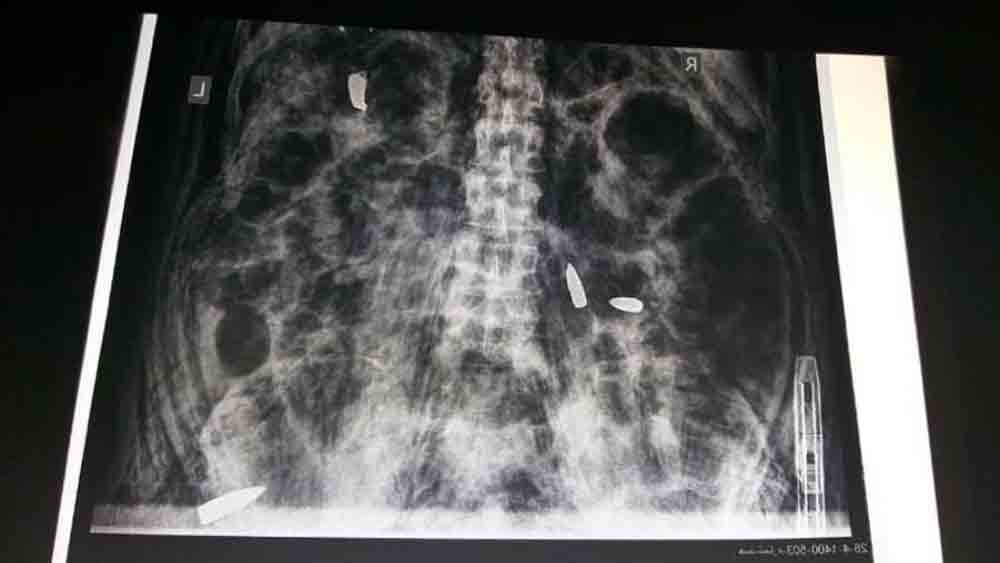

একাধিক গুলিতে দেহ ঝাঁঝরা করে দেওয়ার পরেও তার উপর চালিয়ে দেওয়া হয়েছিল ভারী গাড়ি। যাতে মুখ থেকে ধড়— বিকৃত হয়ে যায় গোটা দেহ। ভারতীয় চিত্রসাংবাদিক দানিশ সিদ্দিকির দেহে এ ভাবেই অত্যাচার চালিয়েছিল তালিবানেরা। দানিশের দেহাবশেষের মেডিক্যাল রিপোর্ট উদ্ধৃত করে সোমবার একটি সর্বভারতীয় সংবাদমাধ্যম ‘নিউজ ১৮’ এমনই জানিয়েছে। ওই রিপোর্টের প্রতিটি ছত্রে ফুটে উঠেছে তালিবানি নৃশংসতার ছবি।

১৬ জুলাই রাতে কন্দহর শহরের স্পিন বোল্দাকে আফগানিস্তান সেনা এবং তালিবান জঙ্গিদের সংঘর্ষে নিহত হয়েছিলেন ৩৮ বছরের দানিশ। সংবাদ সংস্থা রয়টার্সের চিত্রসাংবাদিক হিসাবে সে সময় আফগানিস্তানের সেনাবাহিনীর বিশেষ শাখা ‘আফগান স্পেশাল ফোর্সেস’-এর সঙ্গে খবর সংগ্রহের পাশাপাশি ছবি তোলার কাজ করছিলেন। সে কাজের সূত্রে দু’পক্ষের গুলিযুদ্ধের মধ্যে পড়ে তালিবানদের ১২টি গুলিতে ঝাঁঝরা হয়ে গিয়েছিলেন পুলিৎজার জয়ী দানিশ। তবে মৃত্যুর পরেও তাঁর নিথর দেহের উপর অত্যাচারের মাত্রা কমায়নি তালিবানরা।

আফগান সূত্র জানিয়েছে, কন্দহরের গুলিযুদ্ধে প্রথমে স্‌প্নিন্টারের আঘাত লাগে দানিশের। তবে তাতেও থামেননি তিনি। গুলিযুদ্ধে এক সময় আফগান সেনাদের সঙ্গে একটি স্থানীয় মসজিদে আশ্রয় নিতে বাধ্য হন। তালিবানরা সেখানে গুলি চালাতে শুরু করলে দানিশ চিৎকার করে নিজের পরিচয় জানান। পরিচয়পত্র দেখিয়েও তালিবানদের হাত থেকে রেহাই পাননি। সূত্রের দাবি, সেই পরিচয়পত্র কোয়েটাতে তালিবানদের সদর দফতরে পাঠায় জঙ্গিরা। এর পর ফেসবুক, টুইটারে দানিশের সমস্ত পোস্টও খতিয়ে দেখা হয়। তাতে আফগান বাহিনীর সঙ্গে ঘুরে ঘুরে দানিশের কাজকর্ম দেখার পর তাঁকে নিকেশ করে দেওয়ার নির্দেশ আসে। এর পর মসজিদ থেকে টেনে বার করে দানিশের বুলেটপ্রুফ জ্যাকেট খুলে নেয় জঙ্গিরা। দেগে দেওয়া হয় পর পর ১২টি গুলি। ওই সূত্রের কথায়, ‘‘১২টি বুলেটে দানিশের দেহ ঝাঁঝরা করে দিয়েছিল। বুলেট ঢোকা ছাড়াও দেহ ফুঁড়ে তা বেরিয়ে যাওয়ার জন্যও বেশ কিছু ক্ষত হয়েছিল। ধড় ও পিঠ লক্ষ্য করেই দাগা হয়েছিল সব ক’টি বুলেট।’’ গুলি চালিয়েও ক্ষান্ত হয়নি তালিবানরা। ওই সূত্রের দাবি, ‘‘মৃত্যুর পরও দানিশের দেহ টেনেহিঁচ়ড়ে নিয়ে যাওয়া হয়েছে। এর পর একটি ভারী গাড়ির চাকার তলায় থেঁতলে দেওয়া হয়েছিল দানিশের মাথা-বুক। সে জন্য টায়ারের ছাপ বসে গিয়েছিল দানিশের মুখে-বুকে। মনে হয়, দেহ বিকৃত করার জন্য এইচইউএমভি বা এসইউভি জাতীয় কোনও ভারী গাড়ি ব্যবহার করেছিল তালিবানরা।’’